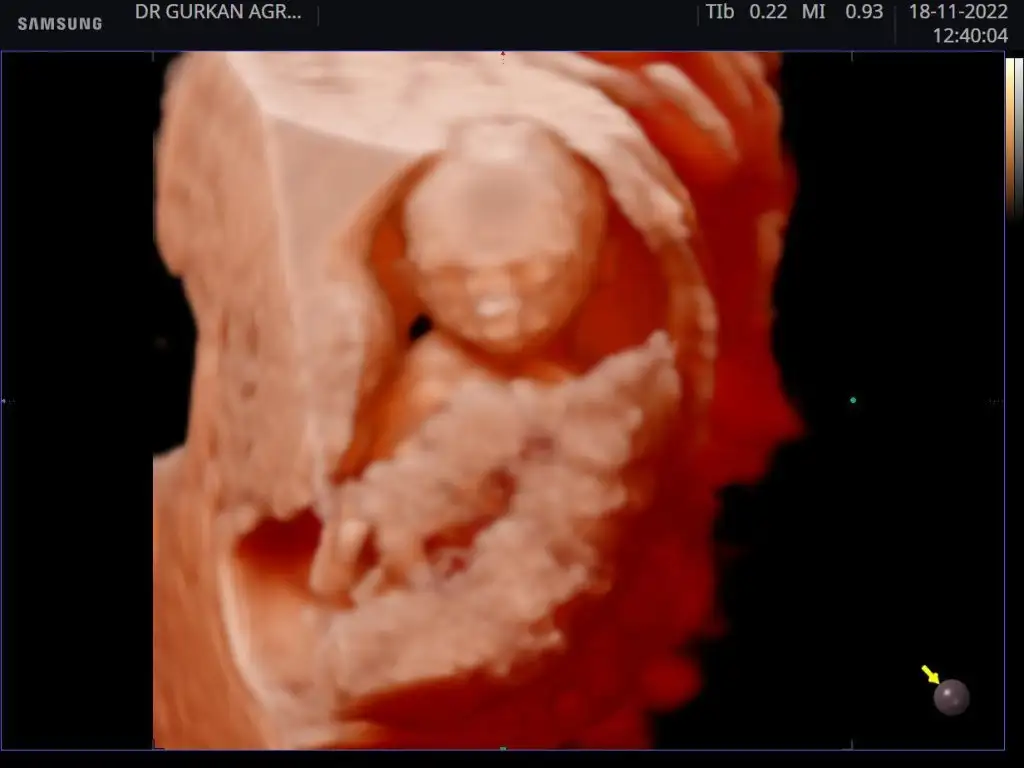

Benim miniğimin 16. Hafta usg si burda bile ağzı burnu belli yaaaSağlıcakla doğur